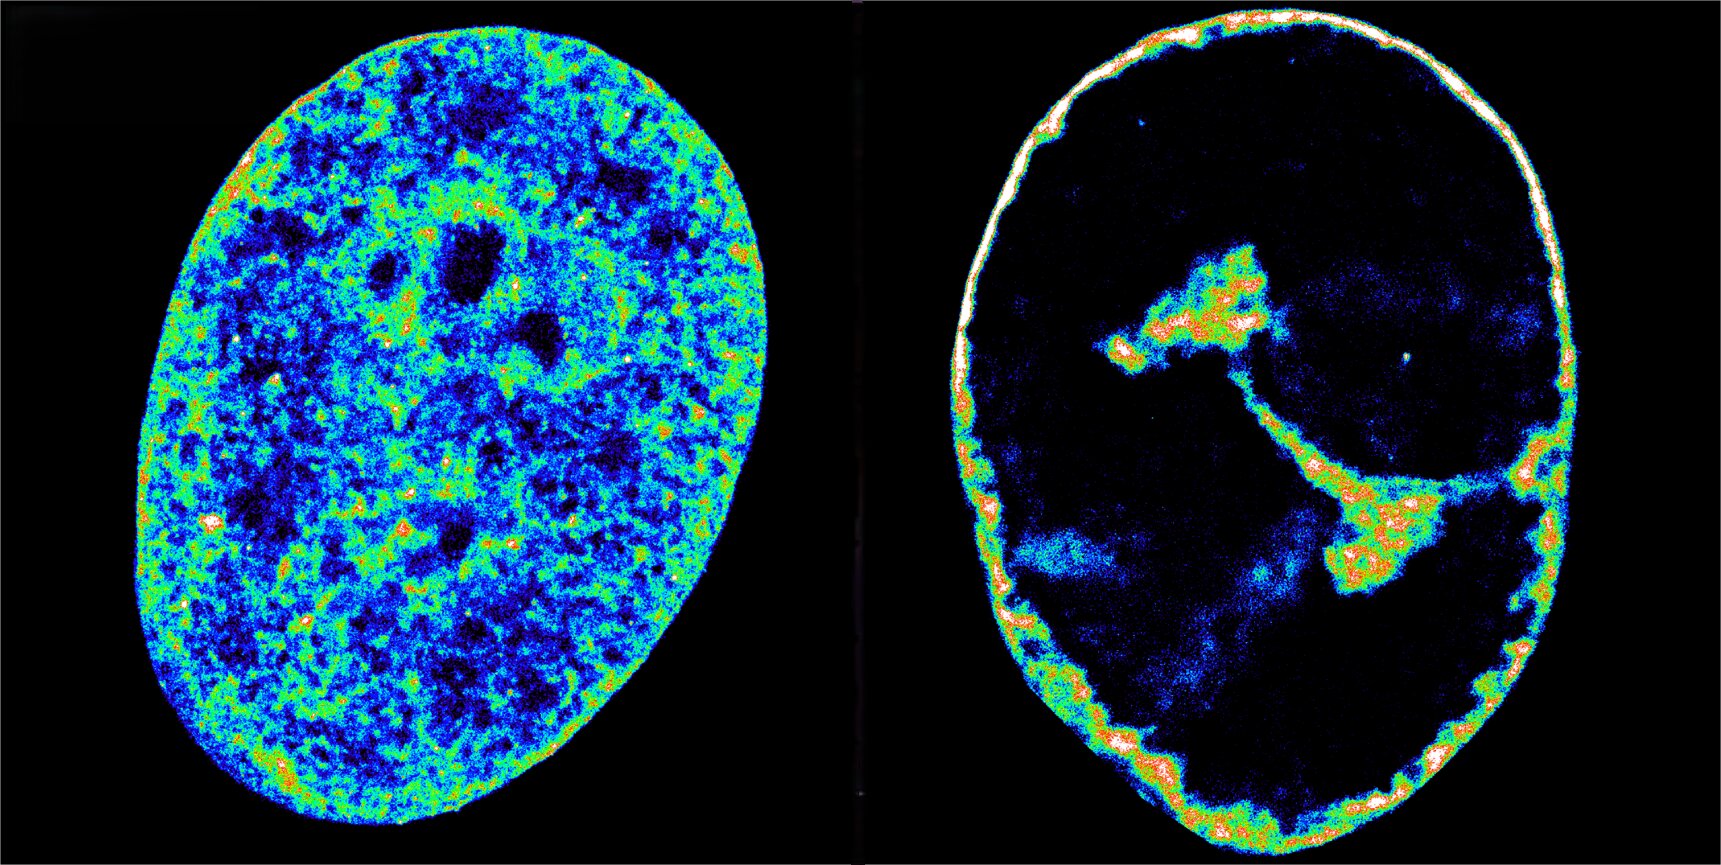

Les chercheurs ont fait leurs résultats en combinant la microscopie en super-résolution, une technique d’imagerie qui peut voir des structures de 20 nanomètres de large, environ 3 500 fois plus minces qu’une mèche de cheveux, avec Hi-C, une technique qui révèle quels bits d’ADN touchent à l’intérieur du noyau. Ils ont utilisé les deux techniques pour acquérir de nouvelles informations mécanistes sur la façon dont HSV-1 détourne les cellules humaines.

Trois heures après l’infection, la plupart des polymérases et une fraction considérable des deux autres facteurs avaient abandonné les gènes humains. Le vol en gros provoque une effondrement de la transcription à travers le génome de l’hôte, ce qui a provoqué la chromatine, l’état naturel du génome humain à l’intérieur des cellules, est écrasé en une coquille dense à seulement 30% de son volume d’origine.

Il s’agissait d’une découverte inattendue, car la structure de la chromatine dicte la transcription. « Nous avons toujours pensé que la chromatine dense a fermé les gènes, mais nous voyons ici le contraire: arrêter la transcription en premier et les compacts de l’ADN par la suite. La relation entre l’activité et la structure pourrait être une rue à double sens », explique le Dr Álvaro Castells García, co-prioritaire de l’étude.